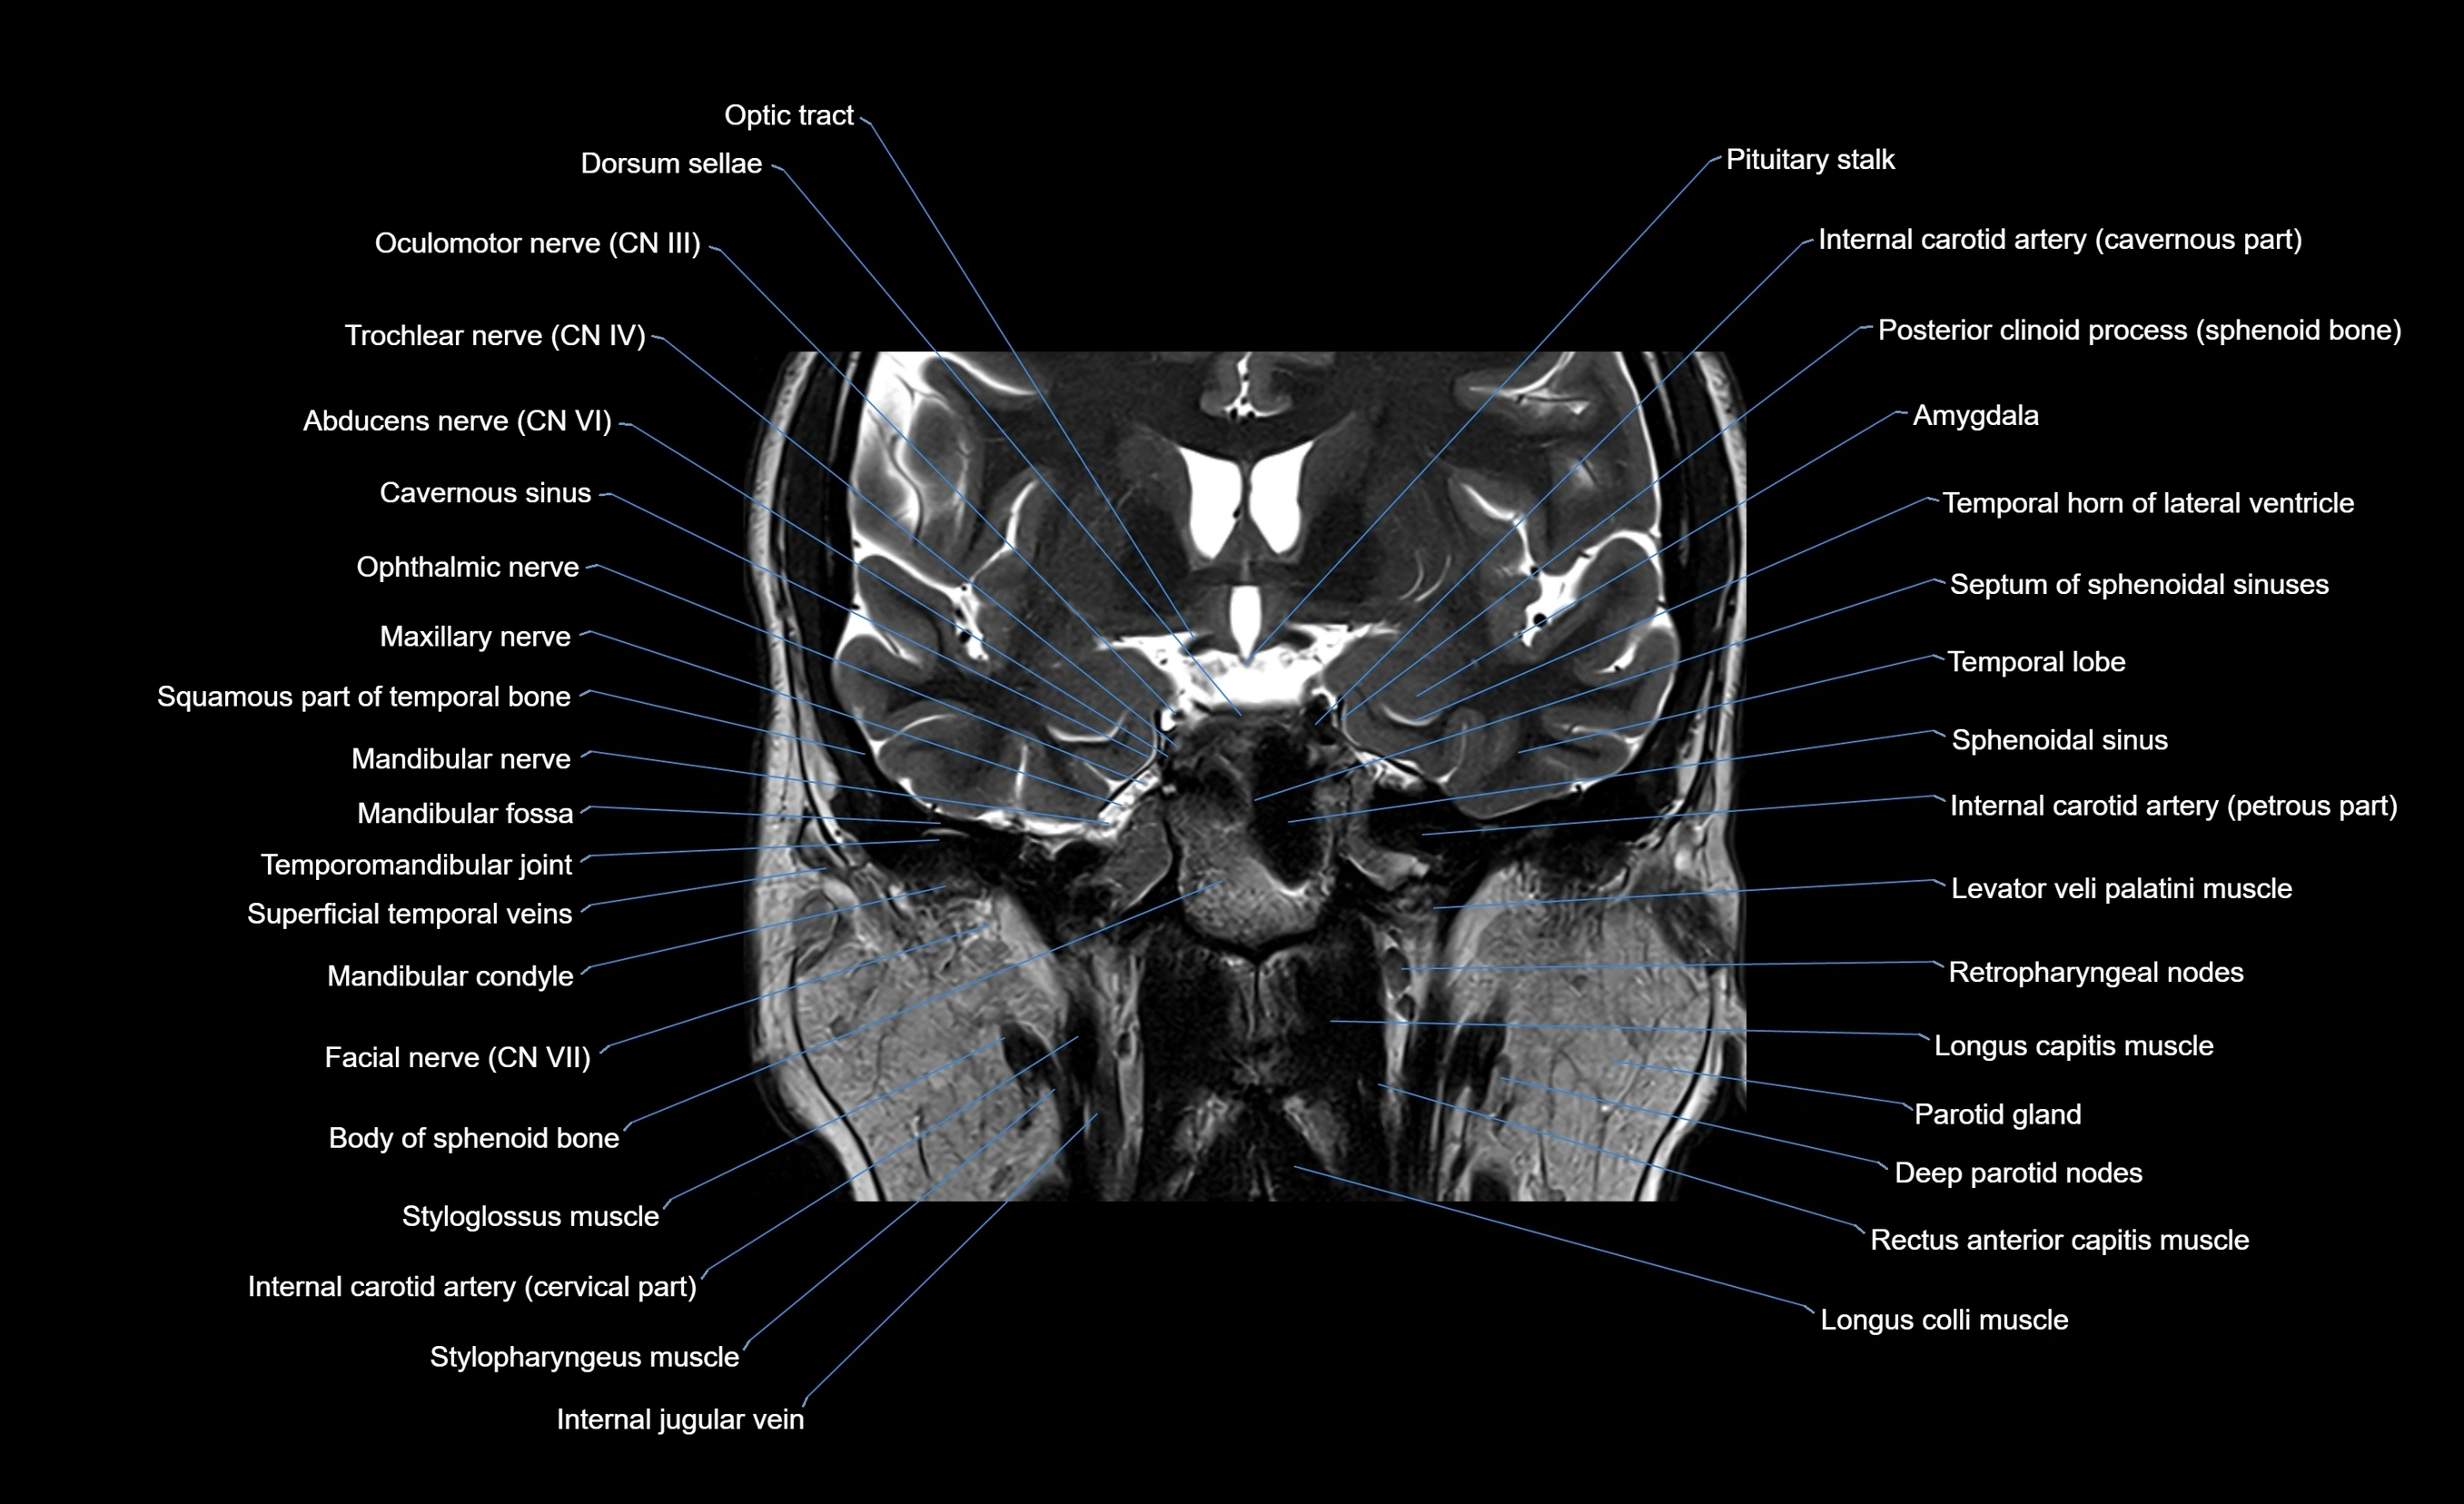

MRI images